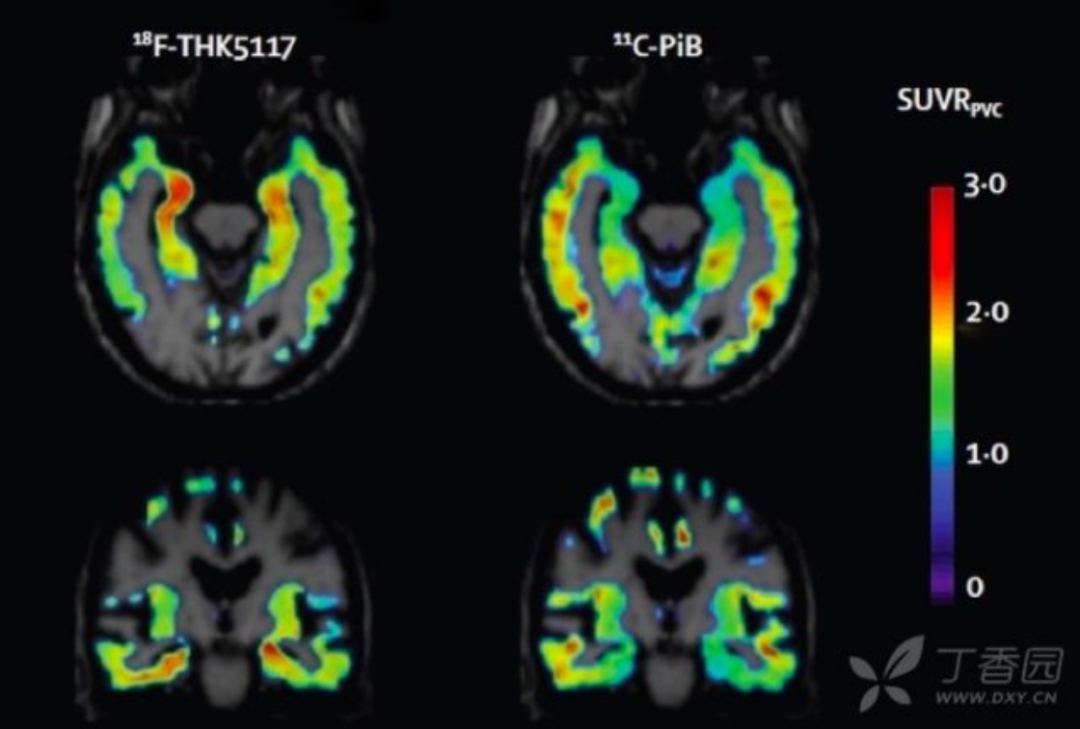

7. tau 蛋白成像 利用 tau 蛋白的氟化配体进行 tau 蛋白成像目前也是研究热点。Tau 蛋白配体聚集与 AD 临床症状符合;且与 Amyloid PET 相比,与基础代谢率减退和脑萎缩更相关。目前 Tau 成像主要用于临床药物试验,对于其临床诊断价值仍需进一步证实。

图 8 AD 患者以 18F-THK5117 和 11C-PiB 为显影剂的 tau 蛋白和 Aβ成像